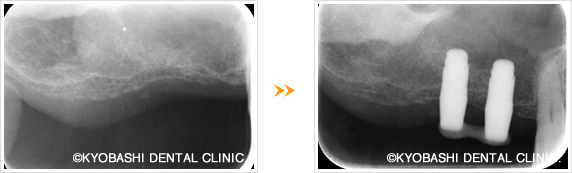

▲当院での下顎前歯のインプラント症例

費用:3本で120万円(税別)

HAインプラントによるソケットリフト(骨造成)の例

ソケットリフト法は、専用の器具を使って上あごの膜(まく)を押し上げて、その部分に人工骨の安全材料を入れて、アゴの骨のの高さを確保する方法です。インプラントを埋入する部分から直接骨を入れて高さをおぎなうので、傷口が小さくて済む利点があります。当院では、患者さんのお体に負担の少ないこのソケットリフト法による骨造成治療で、数多くのインプラントを可能にしております。